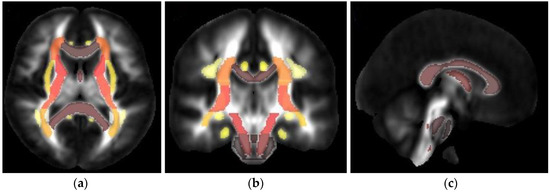

2.4. TBSS and Structural Parcellation